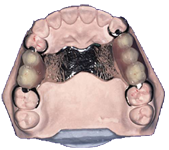

Mobilna protetika

Dentalni laboratorij